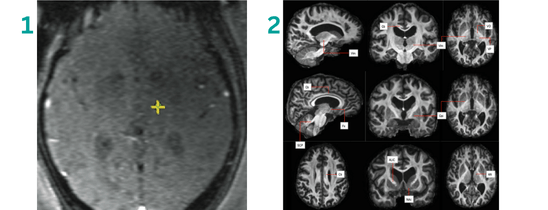

Image 2 shows an example of the FAT-1 images used by neurosurgeons at Queen Square Imaging Centre.

FAT1 imaging overcomes this by giving surgeons a clear, direct view of the individual patient’s Vim, enabling treatment to be far more precise.

The study published in The BMJ Neurology Open marks the first clinical use of FAT1 imaging to guide focused ultrasound treatment for essential tremor. Traditionally, clinicians have relied on generalised brain maps to estimate the location of the target area deep within the brain – the Ventral Intermediate Nucleus (Vim) – which is extremely small and hard to visualise on standard MRI scans.